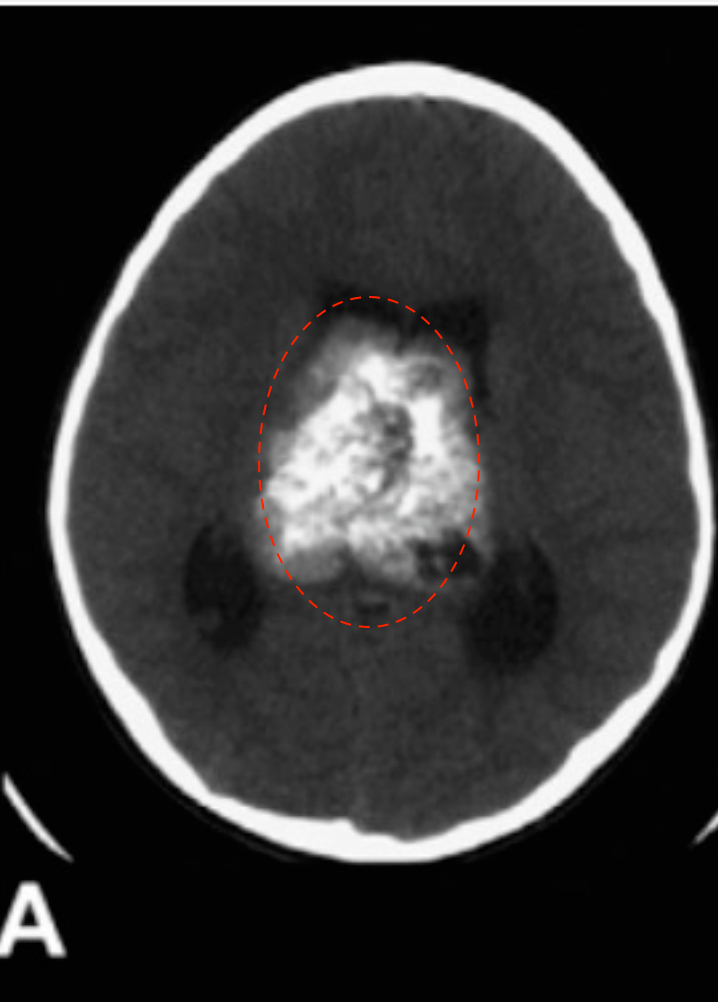

12岁男孩,因出现近3周的头痛和急性恶化而入院治疗。

(A)颅脑CT显示一个大的脑室内肿块伴钙化和瘤内出血并伴有脑积水。